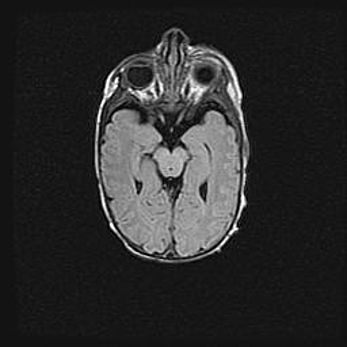

Лейкомаляция с кистозно-глиозной дегенерацией головного мозга.

Возраст: 2 месяца 25 дней

Вес: 6400 г

Окружность головы: 40 см

Срок гестации: 41 неделя

Лейкомаляцию относят к ишемически-гипоксическим повреждениям головного мозга, диагностируемым у новорожденных. При лейкомаляции в головном мозге обнаруживают очаги некроза, возникшие после тяжелой гипоксии и нарушения кровотока. В процессе морфогенеза очаги проходят три стадии: 1) развития некроза, 2) резорбции и 3) формирования глиозного рубца или кисты. Перивентрикулярная лейкомаляция (ПЛ) встречается примерно в 12% случаев среди новорожденных, обычно – у недоношенных детей, причем, частота ее зависит от массы, с которой младенец появился на свет. Наибольшее число малышей страдает лейкомаляцией, если масса при рождении 1500-2500 г.